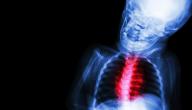

تتمثل أمراض الروماتيزم (بالإنجليزية: Rheumatic disease) بوجود التهاب يؤثر في البُنية الرابطة أو الدّاعمة للجسم؛ وتُعتبر المفاصل أكثرها شيوعاً، وفي بعض الأحيان قد تؤثر هذه الحالة في الأوتار، أو الأربطة، أو العظام، أو العضلات، وتجدر الإشارة إلى أنّ لبعض الأمراض الروماتيزمية تأثيراً في أعضاء الجسم أيضاً، وفي هذا السّياق يُشار إلى أنّ هذه الأمراض قد تؤدي في النهاية إلى فقدان أجزاء الجسم وظائفها، وبحسب الإحصائيّات فإنّ الأمراض الروماتيزمية تؤثر في أكثر من 46 مليون أمريكي، من بينهم 294 ألف طفل.[١]